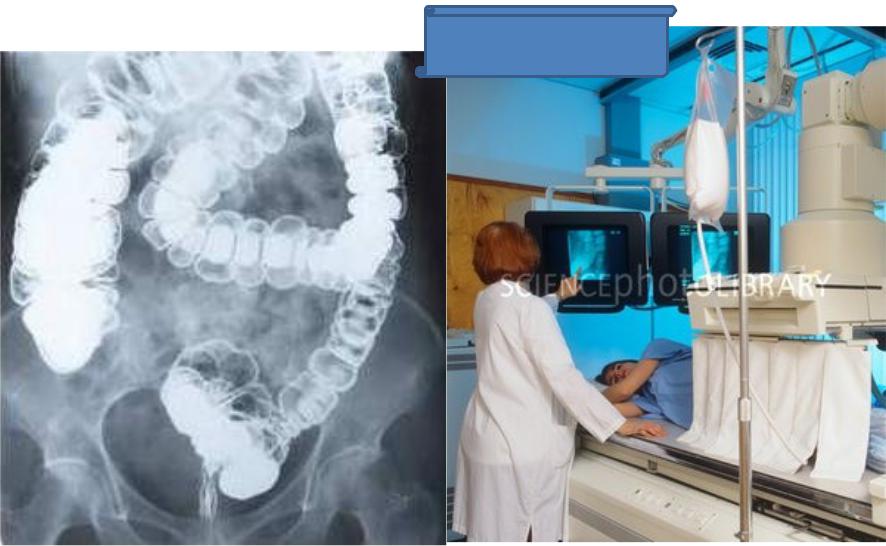

Подготовка к ирригоскопии: необходимые препараты